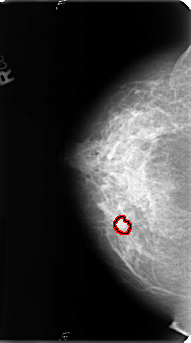

B_3128_1.LEFT_CC

LEFT_CC LINES 4816 PIXELS_PER_LINE 2464 BITS_PER_PIXEL 12 RESOLUTION 50 NON_OVERLAY

FILE: B_3128_1.RIGHT_CC.OVERLAY

TOTAL_ABNORMALITIES 1

ABNORMALITY 1

LESION_TYPE MASS SHAPE IRREGULAR MARGINS ILL_DEFINED-SPICULATED

ASSESSMENT 4

SUBTLETY 2

PATHOLOGY BENIGN

TOTAL_OUTLINES 1

BOUNDARY